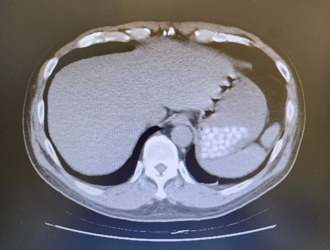

照電腦斷層「胃驚見22顆白點」 急診醫問一句秒笑

急診科醫師蔡瀚嶙經常在社群平台分享工作趣事,近日他幫男病患做電腦斷層檢查,驚見對方的胃出現至少22顆白色顆粒,他跟對方確認是珍珠奶茶的珍珠後默默笑了,將其PO上網引起66萬人次瀏覽、萬人按讚,當中有網友好奇在醫療院做電斷層到底要不要空腹,蔡回說「急診不用」。